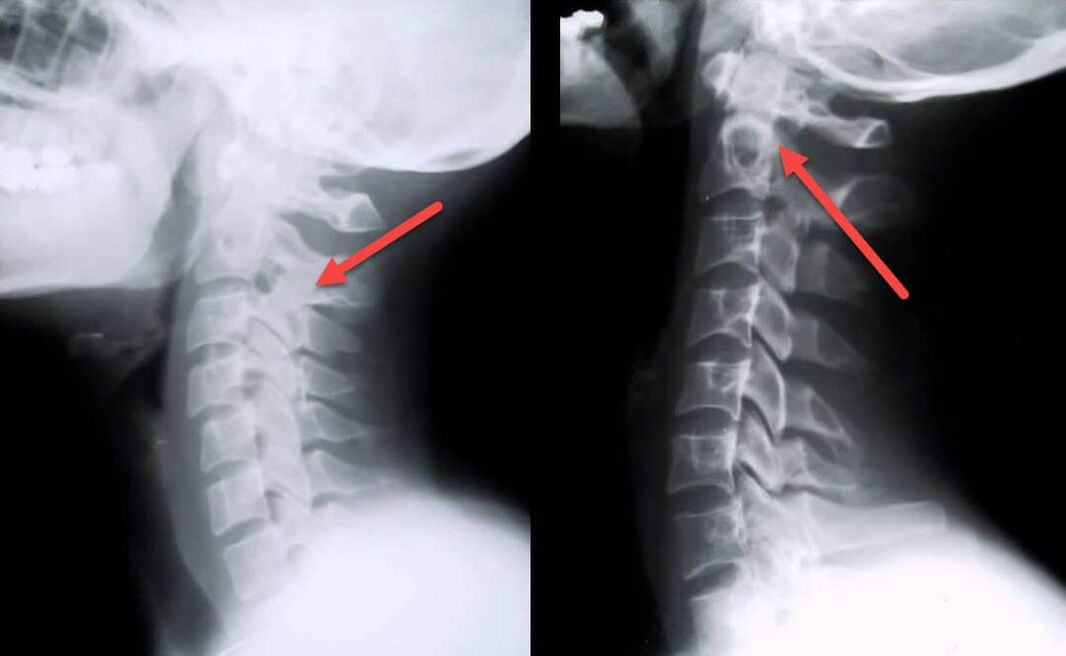

Nejinformativnějším diagnostickým postupem je radiografie. Patologie 1. stupně odpovídají 1. nebo 2. radiologickému stadiu. Výsledné snímky vizualizují typické příznaky onemocnění.

| Rentgenová stadia cervikální osteochondrózy 1. stupně | Charakteristické znaky |

|---|---|

| Fáze 1 | Drobné změny v zakřivení páteře v krční oblasti, postihující jeden nebo více segmentů |

| Fáze 2 | Mírné ztluštění meziobratlových plotének, deformace výběžků necinate, napřímení lordózy, drobné výrůstky kostních struktur |